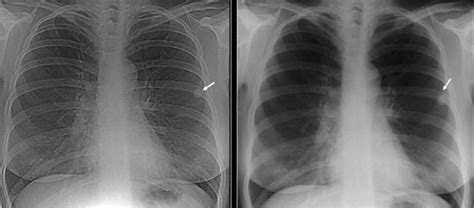

Webentenda a diferença de nódulos no pulmão malignos e benignos,. Se for pequeno, totalmente calcificado e se não apresentar evolução ao longo do tempo, a probabilidade de ele ser benigno é grande. Nesses casos, na maioria das vezes, não precisa ser tratado nem removido. Webo granuloma é um pequeno nódulo, de origem inflamatória, que o organismo forma ao redor de algo que o corpo não reconhece mas também não consegue expulsar. A maioria dos granulomas formados no organismo são lesões benignas, assim como no. Webas radiografias de tórax evidenciaram múltiplos nódulos pulmonares, que a tomografia computadorizada (figuras 1 e 2) mostrou estarem calcificados e escavados. A biópsia pulmonar a céu aberto revelou lesões de natureza inflamatória, constituídas por tecido fibroso maduro, com áreas de calcificação e ossificação infiltradas por. Pequenos linfonodos calcificados no mediastino. Webfora isso, se a causa do granuloma pulmonar for identificada se é infecciosa ou não infecciosa, então o tratamento visa tratar essa condição. Se o granuloma pulmonar é causado devido à infecção por bactérias, então antibióticos serão prescritos para eliminar as bactérias que causam a infecção.

Imagem de nódulo pulmonar de natureza benigna, granuloma. Estou com granuloma residual calcificado lado esquerdo do pulmonar. Estou com granuloma residual calcificado lado esquerdo do pulmonar. É um achado benigno, muito comum e isento de significado clínico. Webem são josé dos campos você pode contar com os atendimentos do dr.